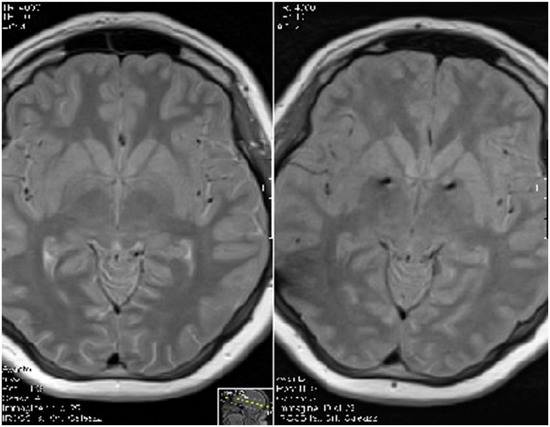

Neuromodulation consists of a variety of invasive and non-invasive therapies for patients with severe neurologic and psychiatric disorders. As an established invasive procedure, deep brain stimulation (DBS) is applied for a variety of pharmacologically resistant neurological and psychiatric disorders. The renaissance of deep brain stimulation (DBS) for essential tremors in 1987 and subsequently for Parkinson’s disease (PD) in Grenoble, France, led only a decade later to DBS for psychiatric diseases, with the first reports published on DBS for obsessive compulsive disorder (OCD) and for Gilles de la Tourette’s syndrome. DBS for the treatment of refractory depression was pioneered shortly after in 2005. Since then, more than 260,000 patients worldwide have been treated with DBS. The indications for DBS have broadened rapidly during the last few decades to other pathologies such as eating disorders, chronic pain, dementia and epilepsy. The U.S. Food and Drug Administration (FDA) approved DBS for essential tremors in 1997, for PD in 2002, for dystonia in 2003 and for OCD in 2009 (under a Humanitarian Device Exemption). Further promising neuromodulation therapies include epidural motor cortex stimulation (MCS) for neuropathic and phantom limb pain, as well as vagus nerve stimulation (VNS) for the treatment of pharmacological refractory epilepsy. Electroconvulsive therapy (ECT), a non-invasive therapy, is applied for severe major depressive disorder, bipolar affective disorder or schizophrenia. Other non-invasive therapies are transcranial electrical stimulation (TES) and transcranial magnetic stimulation (TMS), used for a variety of neurological and psychiatric conditions. This Special Issue aims to review the latest evidence on the effectiveness and safety of these neuromodulation modalities in neurological and psychiatric disorders and will examine the potential underlying molecular mechanisms of the applied techniques.